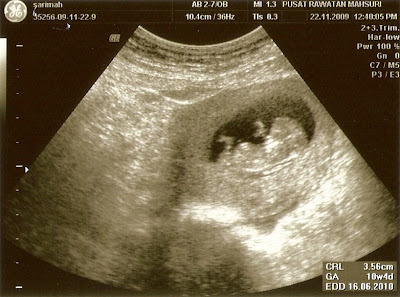

Semalam genap sthn sy n mr hubby kehilangan bb kami.... 4 bln dlm kandungan adalah saat plg manis ummi bersama baby.. ummi x kan lupakan baby, seorg insan yg ummi tunggu kelahiranmu tp percaturan Allah adalah yg terbaik.. tarikh ni akan ummi ingat sampai bila2..